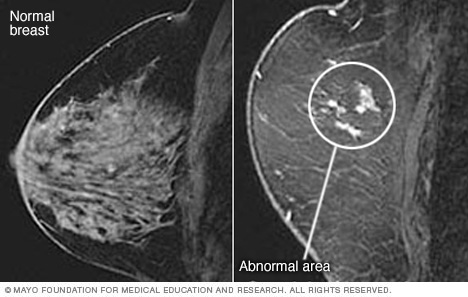

Magnetic resonance imaging (MRI) of the breast, also called breast MRI, is a test used to find breast cancer. It also can help rule out breast cancer when there are other problems in the breast.

A breast MRI makes pictures of the inside of the breast. It uses powerful magnets, radio waves and a computer to make images with a lot of detail.

A breast MRI can find problem areas within the breast. A breast biopsy might follow a breast MRI to see if the problem areas found on the MRI are cancer.

A doctor specializing in imaging tests, called a radiologist, reviews the pictures from the breast MRI. A member of your health care team talks to you about the results of the test.